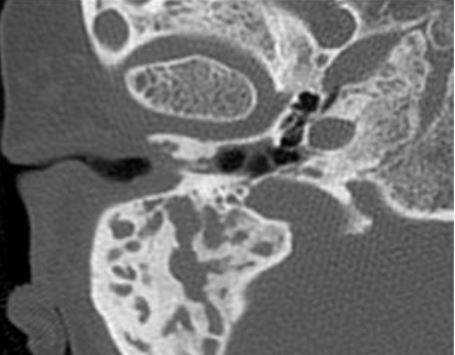

Шваннома лицевого нерва: осевое КТ-изображение (костное окно) демонстрирует расширение ганглия, присутствует однородная масса мягких тканей (стрелка)